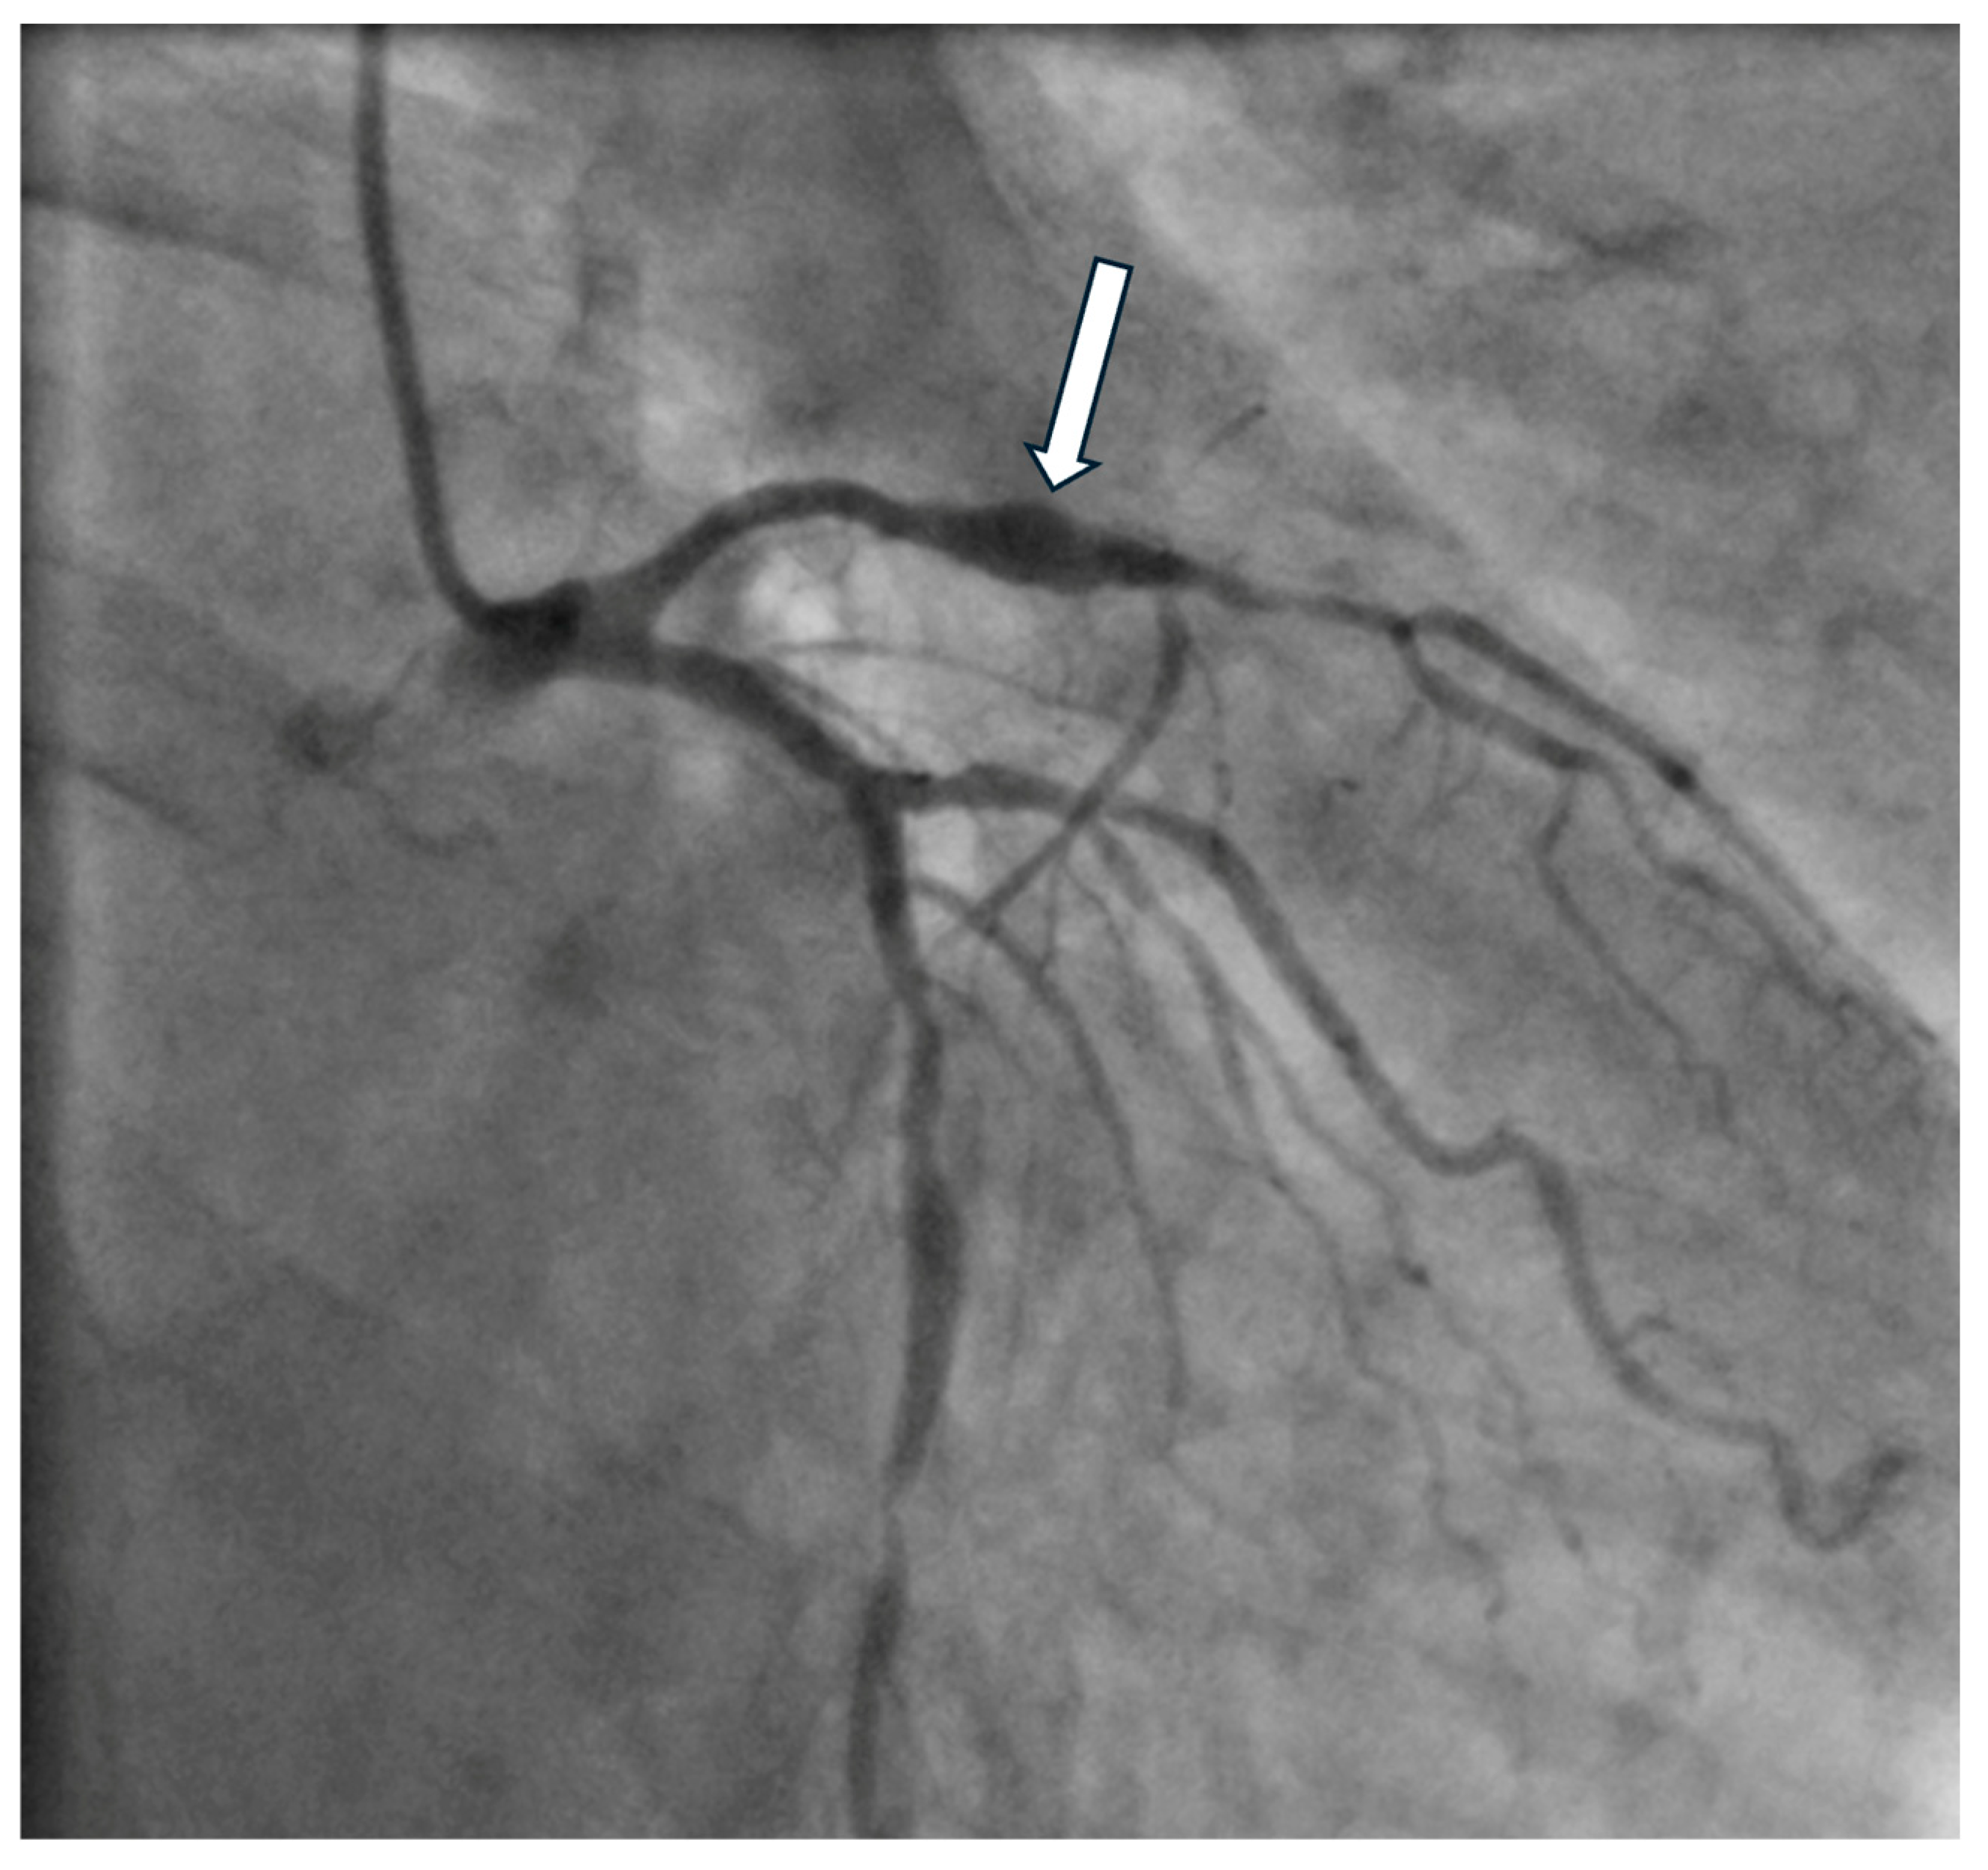

4. Diagnostics